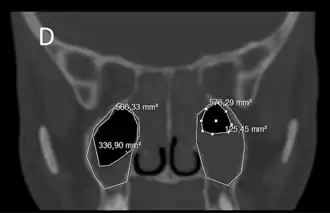

En la gran mayoría de los casos de sinusitis aguda, el diagnóstico es exclusivamente clínico, y no hay necesidad de realizar exploraciones y pruebas complementarias.[13] En casos con sospecha de complicaciones, que son excepcionales, se pueden realizar exámenes vídeo-endoscópicos, así como un TAC (tomografía axial computarizada) o una tomografía computarizada de haz cónico (CBCT: cone beam computed tomography). Es de destacar que la utilización de los rayos X convencionales para el diagnóstico de las sinusopatías, antiguamente práctica habitual, está actualmente desaconsejada, debido a la alta tasa de fallos que este tipo de examen presenta para los senos faciales. Los fallos de los rayos X convencionales para el diagnóstico de las sinusopatías abarcan tanto falsos negativos como falsos positivos. Por otra parte, en el caso de la sinusitis crónica, hay que tener en cuenta que las celdillas etmoidales representan un importante obstáculo anatómico que restringe en gran medida las posibilidades de los exámenes vídeo-endoscópicos en aquellos pacientes en los que estas no hayan sido retiradas por completo por procedimientos quirúrgicos, es decir, en la gran mayoría de la población. Son necesarios procedimientos como las tomografías computarizadas, que proporcionen imágenes de las zonas a las que no puedan acceder los endoscopios. Las tomografías computarizadas de haz cónico (CBCT) suelen ser empleadas principalmente en otorrinolaringología y en odontología y ofrecen tres ventajas importantes con respecto a las axiales (TAC): En primer lugar las imágenes resultantes pueden ser también tridimensionales en lugar de solamente bidimensionales; en segundo lugar requieren de una dosis de radiación mucho más baja; y en tercer lugar proporcionan una resolución de imagen más alta. Las tomografías computarizadas son en general de especial importancia en relación con los senos paranasales, dado que no son excepcionales los casos de sinusitis crónica que cursan sin hallazgos en exploraciones video-endoscópicas y sin un solo síntoma aparente que se asocie normalmente a una sinusitis, aparte de un decaimiento general. La ausencia de tales síntomas y de cualquier otro hallazgo puede a su vez inducir erróneamente a sospechar problemas mentales o emocionales: existen casos en los que sin la ayuda de un procedimiento comparable al de la tomografía computarizada resulta imposible detectar una sinusitis crónica. En resumen, la sinusitis, si es aguda, suele ser muy fácil de diagnosticar, gracias a sus síntomas; y por el contrario, si es crónica, puede ser extremadamente difícil de diagnosticar, si no es gracias a la tomografía computarizada.